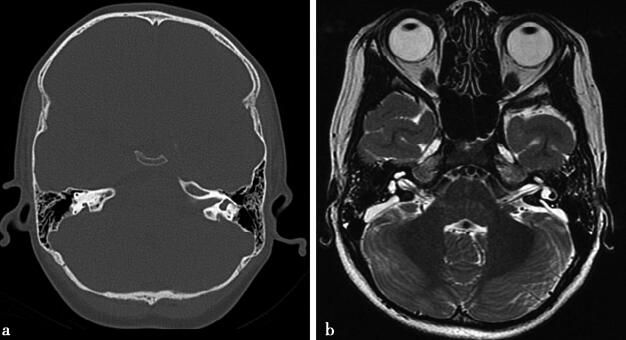

图1a,CT显示双侧前庭导水管扩张呈三角形。1b,双耳T2WI显示双耳内淋巴囊扩张。1c~d,内耳水成像显示双侧内淋巴囊扩张

轴位CT可见扩大的前庭导水管呈宽大三角形、裂隙状、囊袋状等。从半规管总脚到前庭导水管外口的1/2处直径(中点直径)>1.5mm,即诊断为前庭导水管扩大;或前庭导水管外口宽度即前庭导水管骨嵴至总骨脚后侧壁的垂直距离>2.0mm。MRI显示内淋巴囊扩大,呈三角形、椭圆形、弧形等,贴近于小脑半球表面,其前端内淋巴管增粗,边缘光整。